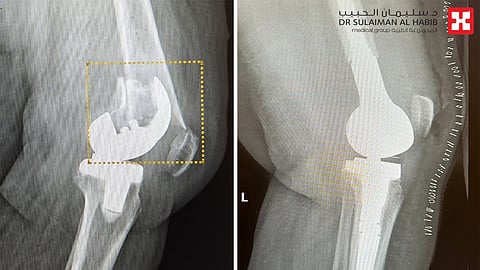

وقال د. دحدولي الحاصل على الزمالتين الكندية والبريطانية، أن المراجعة جاءت إلى المستشفى وهي تشتكي من عدة أعراض أبرزها، عدم القدرة على المشي، وآلام حادة في الفخذ، وأجريت لها عقب وصولها مباشرة سلسة من الفحوصات الدقيقة، وأظهرت صور الأشعة وجود كسر في عظمة الفخذ، أعلى مفصل الركبة المستبدل، ودرس الفريق الطبي الحالة، وخلص إلى خيارين علاجيين، الأول هو تثبيت الكسر، والثاني هو إزالة المفصل الصناعي واستبدال الجزء السفلي من عظمة الفخذ بجزء معدني مع تركيب مفصل معدني آخر، وفي النهاية اختار الفريق الطبي الخيار الثاني، وذلك لارتفاع احتمالات فشل الثبيت.

وأضاف د. دحدولي أن الفريق الطبي أجرى جراحة للمراجعة تم فيها استبدال مفصل الركبة بآخر مخصص لحالات الأورام والمفاصل المعقدة، ومن ثم إزالة الجزء السفلي المكسور من عظمة الفخذ والاستعاضة عنه بقضيب معدني، واستمر التدخل الطبي قرابة الـ "3" ساعات ومضى بسلاسة، وتكللت جهود الفريق الطبي ولله الحمد بالنجاح التام، ونقلت المراجعة إلى غرفة التنويم بمؤشرات حيوية مستقرة، وتحسنت حالتها وتمكنت من المشي في اليوم التالي، واستمر تحسنها مع العناية الطبية الحثيثة والعلاج الطبيعي قبل أن تغادر المستشفى بعد عدة أيام من الجراحة.